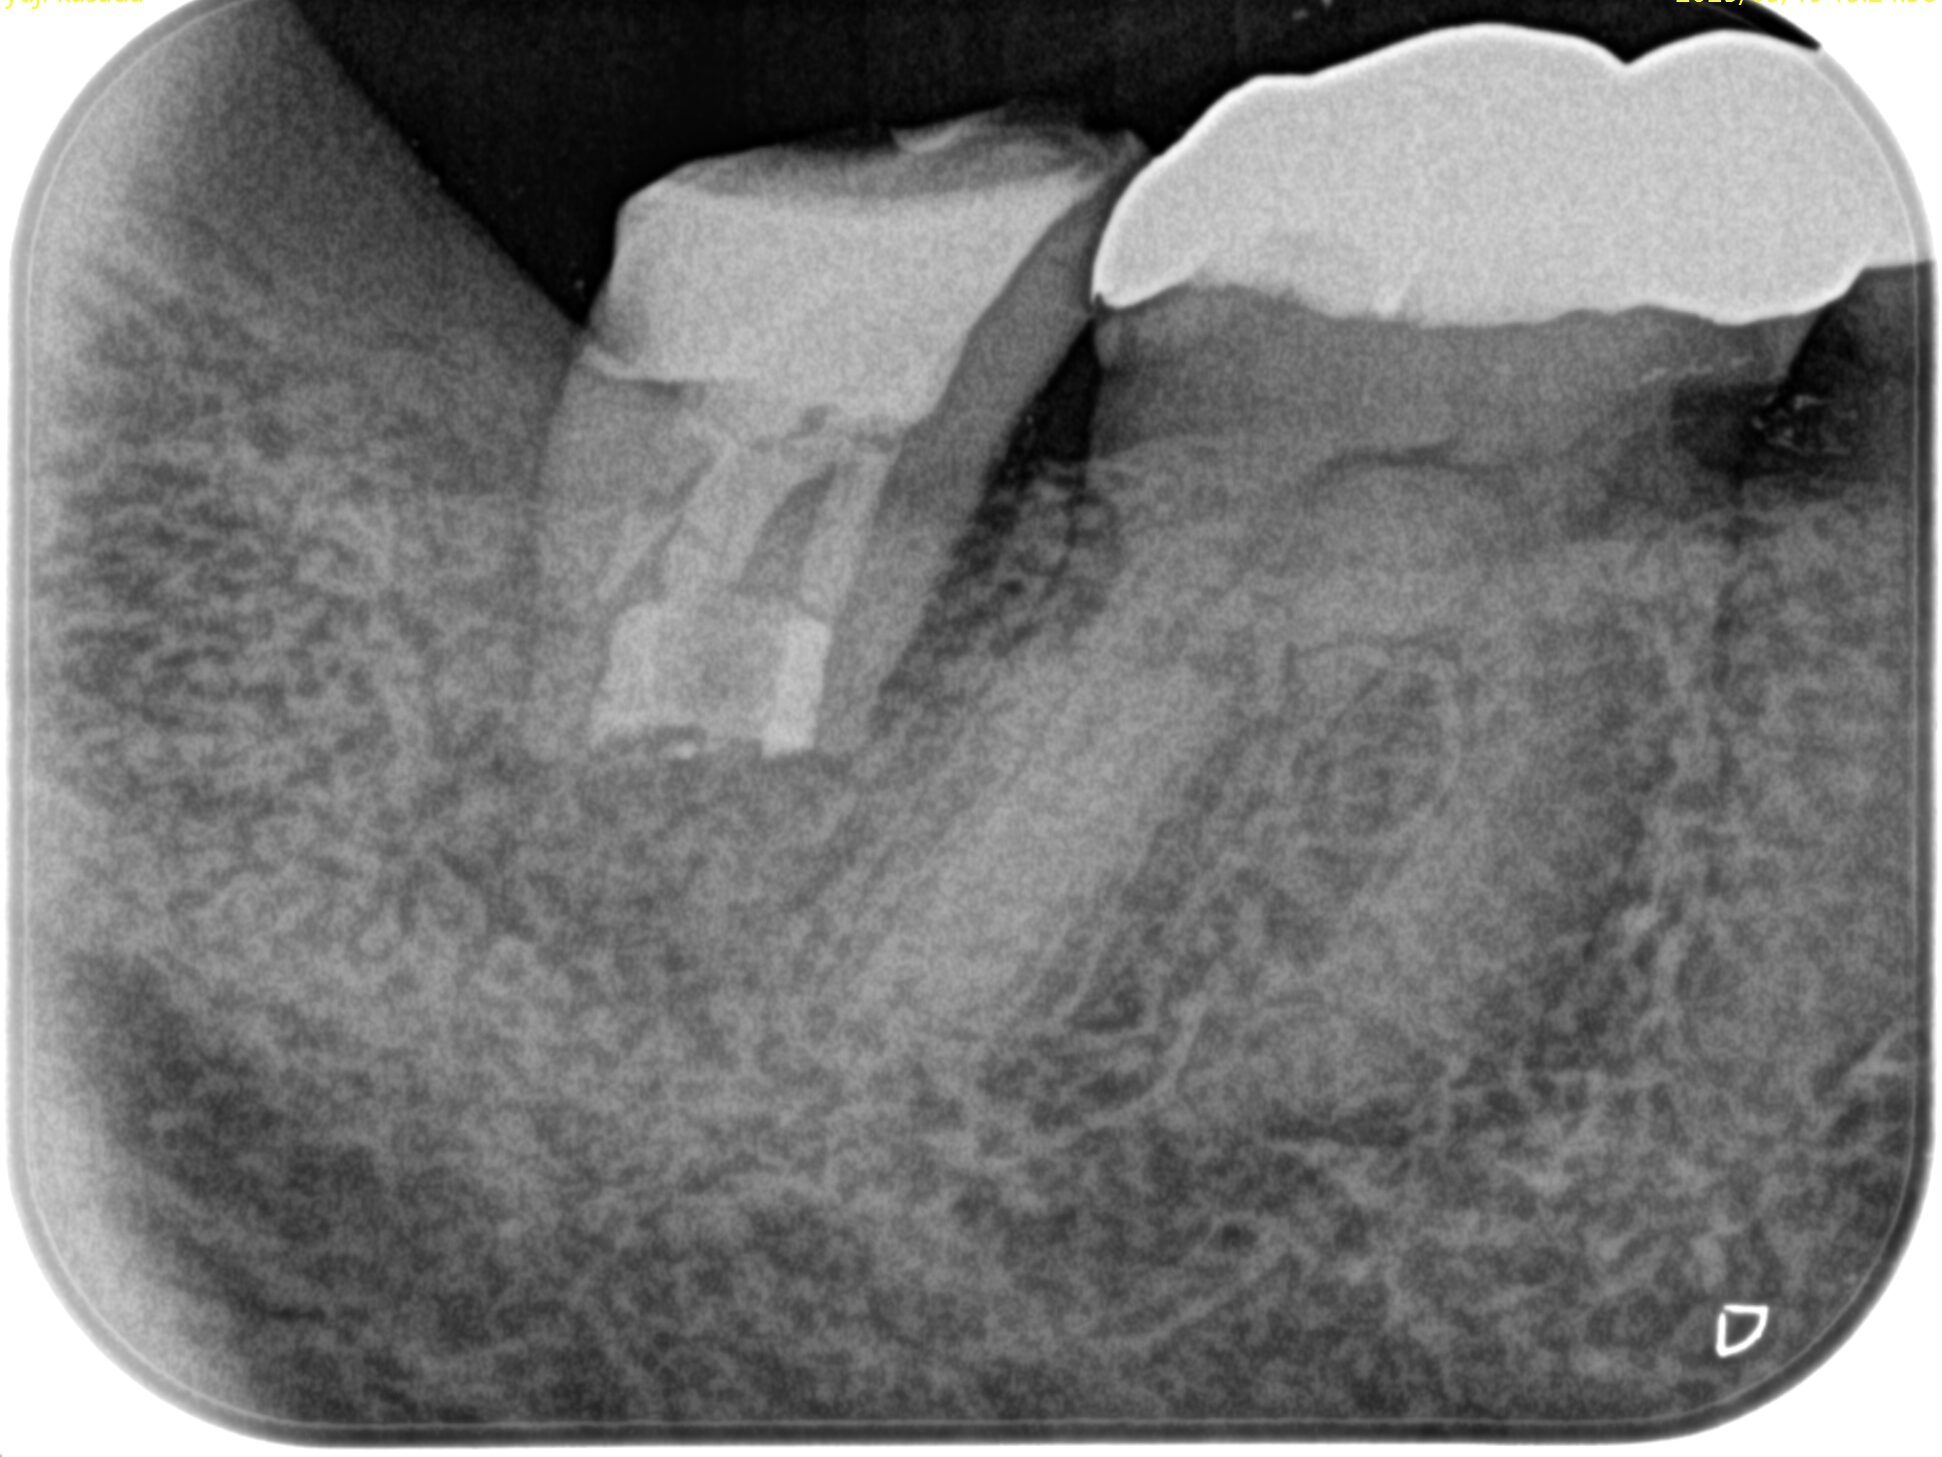

PA(2025.5.19)

確かに…

折れていると言われかねない状況だ。

が、何度も言うが

歯牙が折れているかどうか?は、その歯を抜歯して口腔外に出して直視しないとわからない

のである。